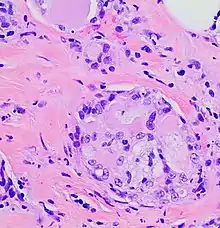

The microscopic histopathology of H&E-stained MSC tumors generally shows well-circumscribed solid tumors with multiple microcysts[13] and sheets of epithelial cells containing numerous vacuoles in their cytoplasm, signet ring cells (i.e. cells with one large cytoplasmic vacuole termed a globule), and extracellular droplet-like secretions resembling the cytoplasmic globules.[2] The sheets of cells are separated by bands of connective tissue.[5] In occasional cases, the cells in MSC tumors are arranged in a papillary (i.e. finger-like)[17] or tubular[14] pattern. The extracellular microcysts and intracellular vacuoles and globules stain red when stained with the H&E stain, consist of sulfated glycosaminoglycans and mucin-containing material,[4] and are identified using periodic acid-Shiff, PAD diastase, or Alician blue stains.[15] The term “secretory” for MSC is in recognition that the tumor cells vacuoles and globules are secreted extracellularly to give the tissues their microcystic appearance.[8] At least 2 cases of MSC had sarcoma-like malignant cells in portions of their tumors and a rapidly metastasizing disease.[18][19]